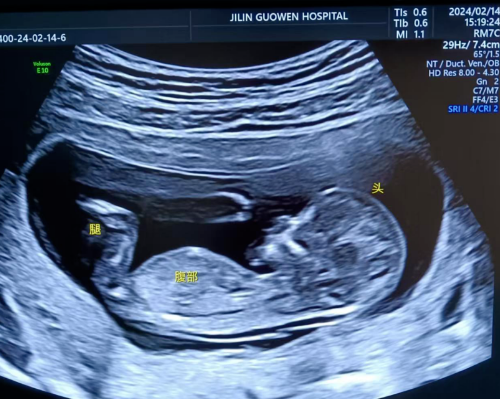

品質(zhì)國文 | 寶媽看過來!胎兒NT彩超免費(fèi)檢查

寶媽看過來!胎兒NT彩超免費(fèi)檢查長春國文醫(yī)院支持國家優(yōu)生優(yōu)育政策,回饋寶媽,NT彩超檢查免費(fèi)。那么,什么是NT檢查呢? 閱讀量:1212